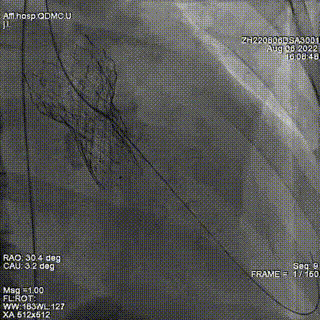

释放第三枚封堵器,选用6mmADOII,释放后造影显示无明显瓣周反流。

术后超声提示微量瓣周反流。